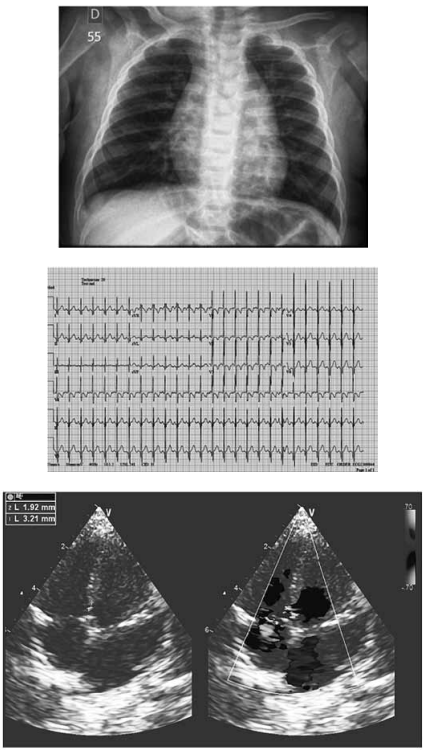

Lactente de 6 meses, com peso atual de 8 kg, apresenta ganho de peso adequado e sem sintomas cardiovasculares segundo a genitora. Exame físico: bom estado geral, corada, hidratada, anictérica, acianótica, afebril, ativo, reativo a estímulos, FC 128 bpm; saturação periférica de O2 de 97% em ar ambiente, ritmo cardíaco a dois tempos com bulhas normofonéticas, sopro sistólico em borda esternal esquerda baixa irradiando em faixa 4/6+, sem visceromegalias, pulsos normopalpáveis e simétricos.

Com base nos dados apresentados, qual seria o diagnóstico da malformação cardiovascular apresentada?